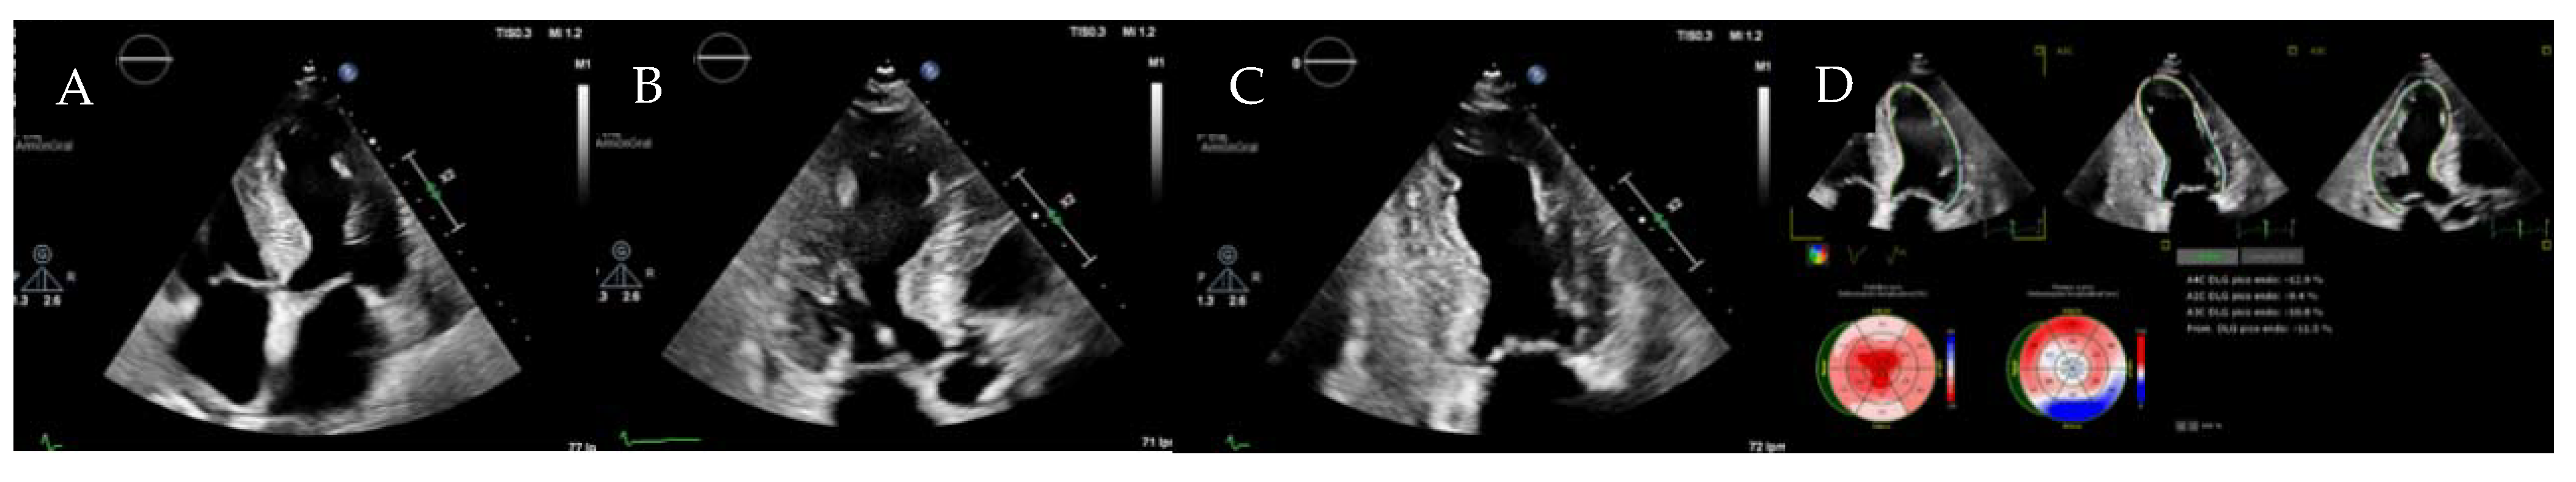

5. Arrhythmogenic Cardiomyopathy